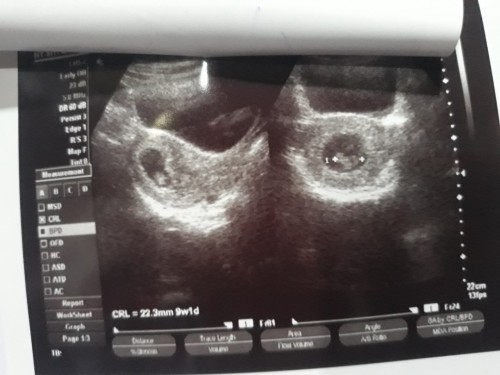

Bunda saya ingin bertanya kehamilan 10minggu usg masih kantongnya aja janinnya belum ada normal kah

aku 9 minggu udah keliatan bun janinnya